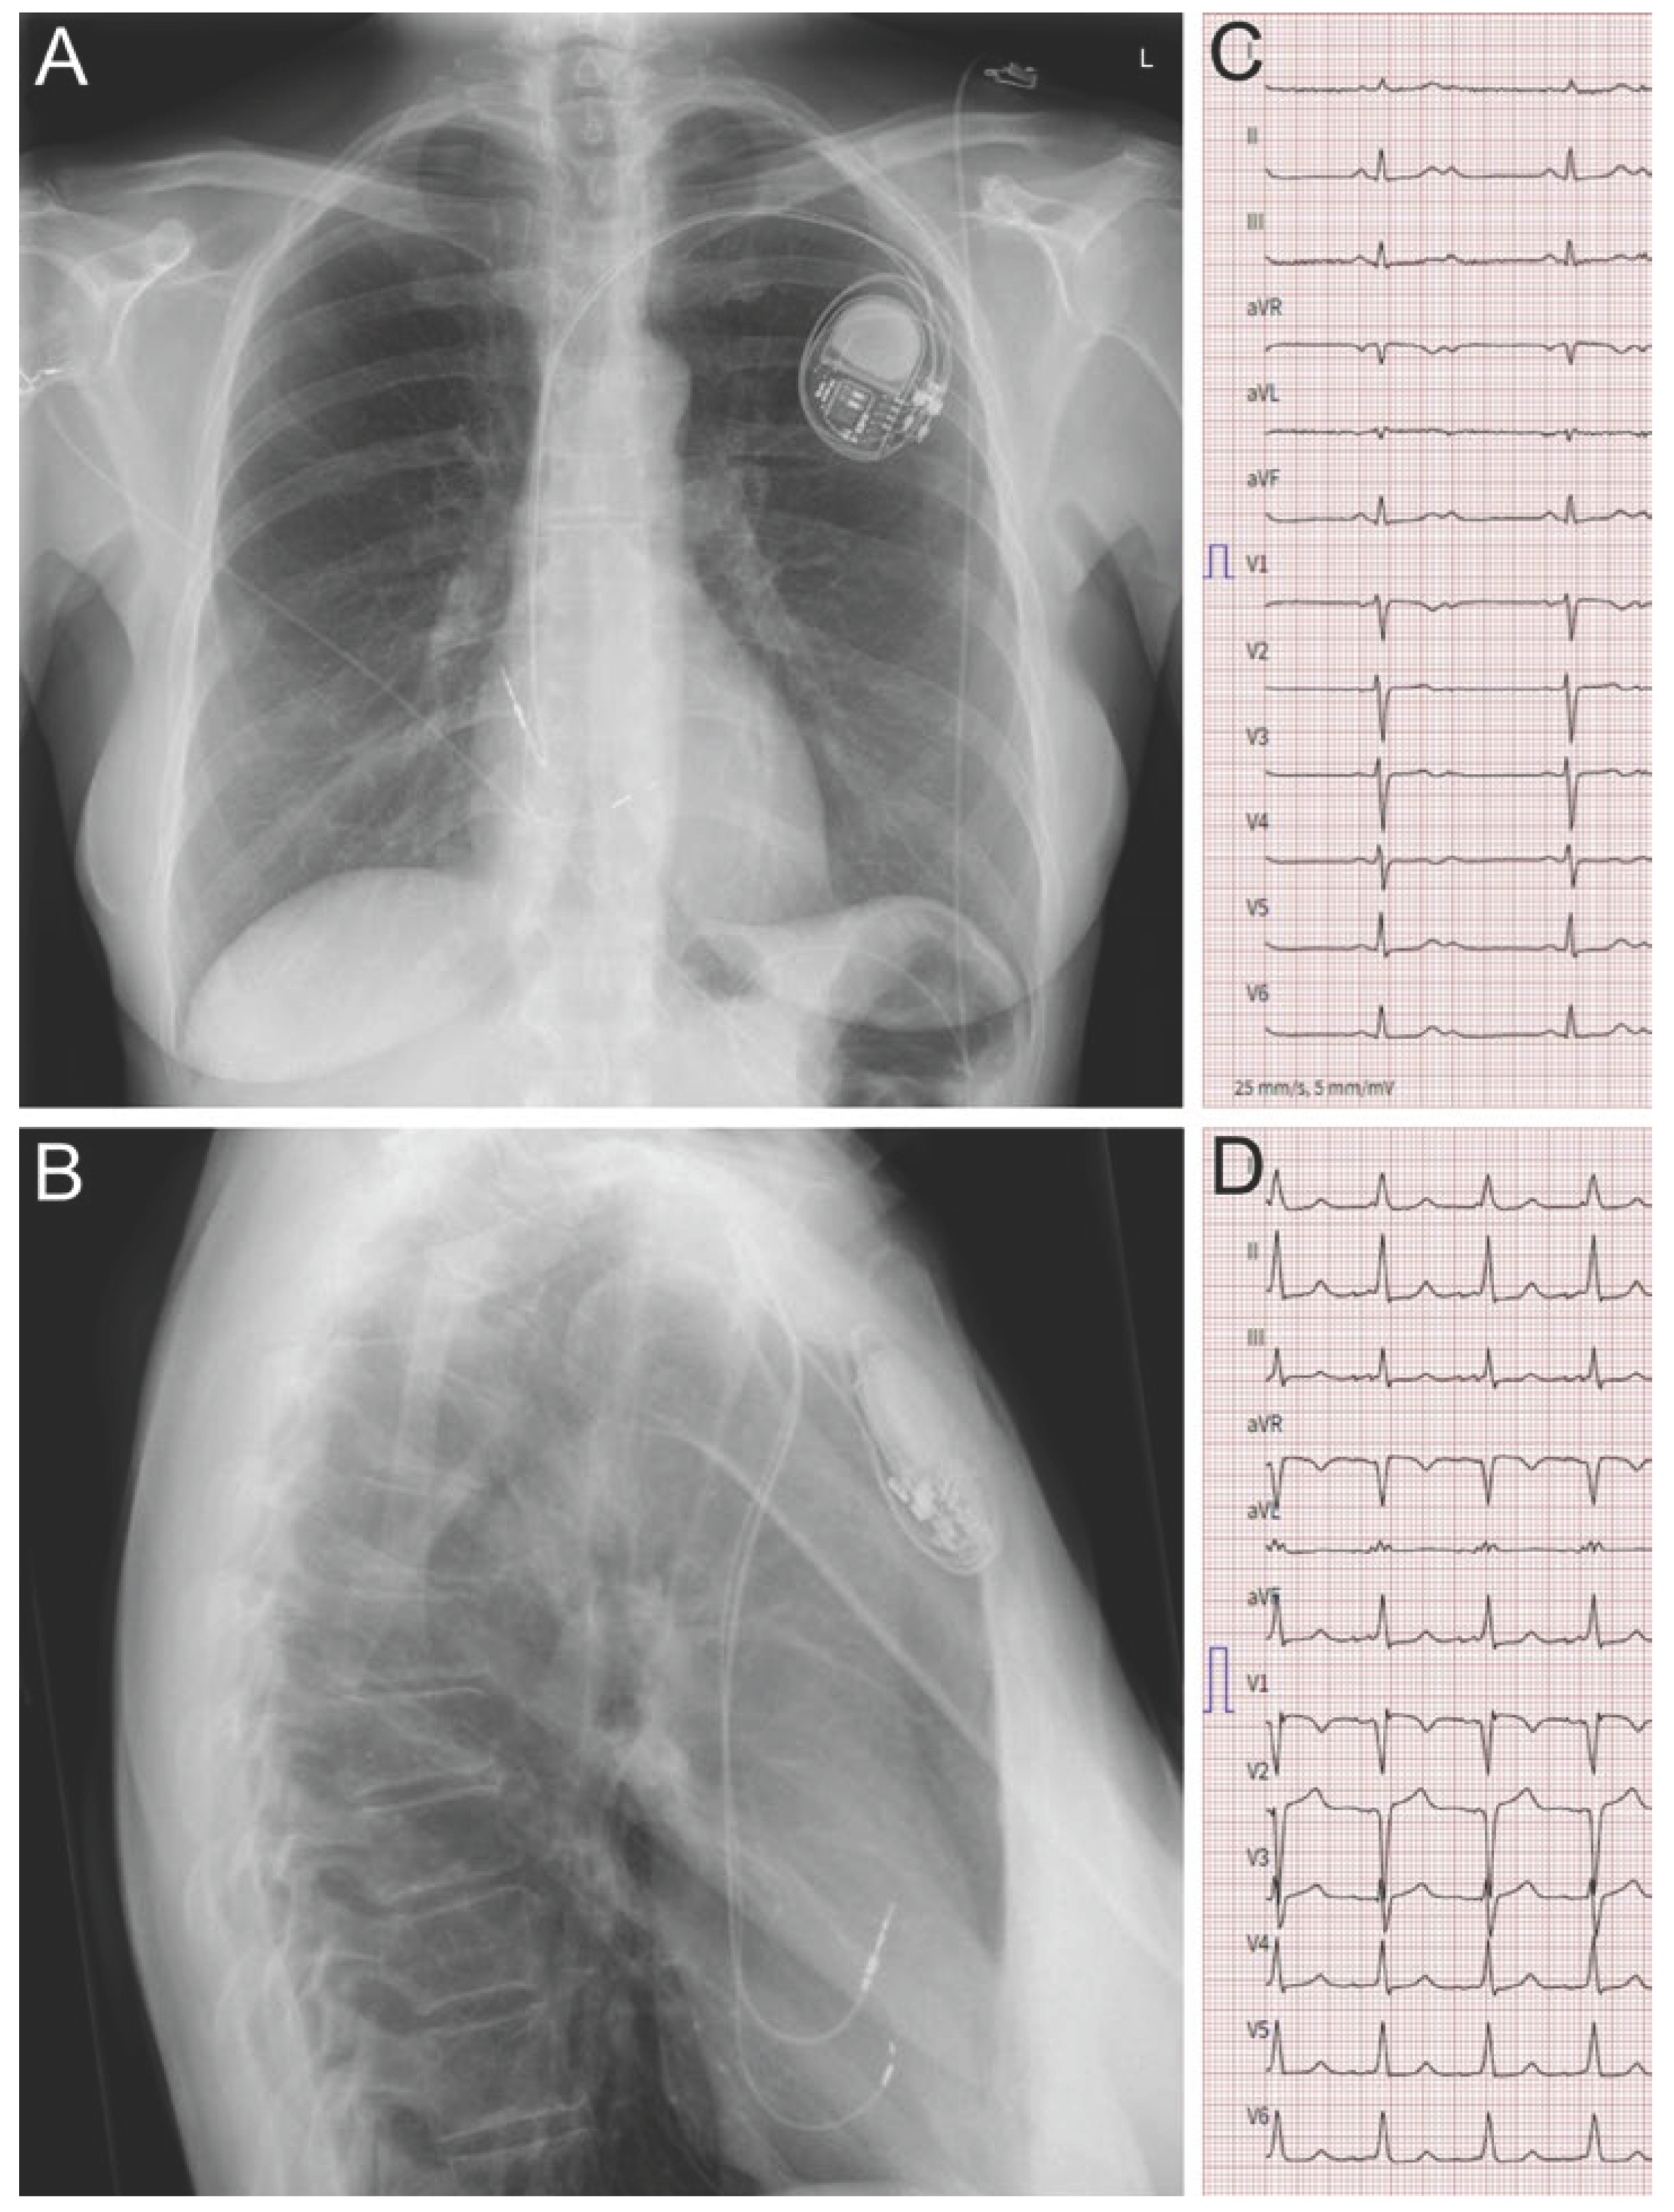

To implant the lead into the left bundle branch (LBB), the interventricular septum needs to be penetrated almost completely as the LBB lies in the LV subendocardium. To identify a suitable site for starting the lead drilling process on the right ventricular side, fluoroscopy and pace mapping are used. The lead is forced gradually through the septum using three-dimensional sheaths. Conventional stylet-driven or lumenless leads may be used. During drilling, continuous unipolar pacing is performed to monitor the fixation progress through the septum. Specific criteria on the 12-lead ECG indicative for LBB capture, repetitive unipolar impedance measurements and septography may provide information to avoid septal perforation. Positioning of the lead in the LBB usually results in relatively narrow QRS complexes (110-120ms, Figure 2), albeit the right bundle and the left anterior bundle may not always be captured in contrast to HBP, which – thus – may be considered the more physiological CSP variant. Combining the LBB lead with a conventional RV lead may further improve electrical activation of the ventricles.

Figure 2. Implantation of a conduction system pacemaker in a 62 year old patient without known heart disease and symptomatic 2:1 AV block. Panels A and B show the X-ray in p.a. (A) and lateral (B) projection. The ventricular lead is fixated in the interventricular septum in left bundle position. Panel C shows the ECG prior to implantation with 2:1 AV block and a narrow QRS complex. Panel D shows the ECG after implantation and bipolar ventricular simulation. The paced QRS duration of circa 110 ms and an r’ is visible in V1. The short R-wave peak time in V6 of circa 65 ms and a V6V1 interpeak interval of circa 40 ms indicate successful recruitment of the conduction system.